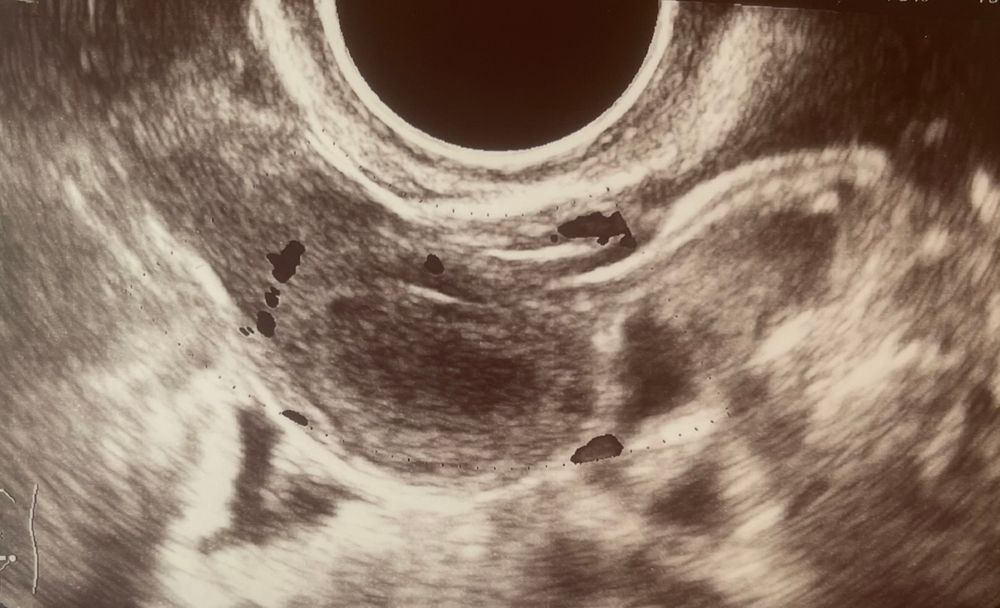

Ангелина, вы видите миому тут? Или плодное яйцо? Просто не поняла)

Карина Карина, я не дописала. ПЯ тут нет.

Но, то что на картинке очень похожа на миому

Карина Карина, интуитивно)) может и не оно, я же говорю, могу ошибаться) но очень похоже, а светлое пятнышко похоже на эмбрион

Может оно, могу ошибаться конечно)